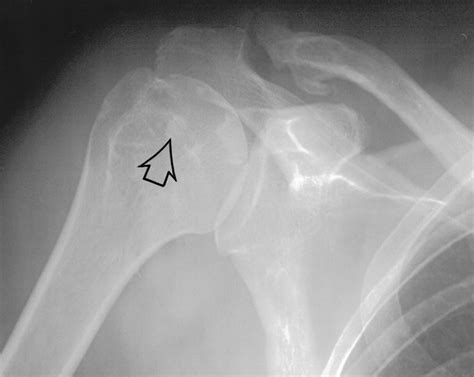

X-Ray The primary imaging tool used to visualize the calcium deposits in the tendon.